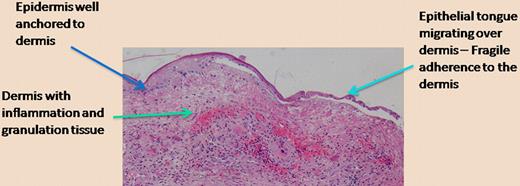

This type of work, while focused on a rare genetic disease that results in mechanical skin fragility and difficult-to-heal wounds, has ramifications for other aspects of tissue integrity and wound healing. A delicate balance exists between anchoring of epithelia (like in skin) to underlying structures, the necessity for cells to migrate upon tissue injury, and the traction required for a more “temporary” anchoring of cells as they migrate.7 The figure is offered as a telling histologic photomicrograph of a chronic wound in which the epidermis is finally migrating over the underlying dermis. As shown on the left side of the figure, away from the wound where the epidermis is thicker, one can expect that the anchoring of the epidermis to the dermis, for example, through type VII collagen, is strong. However, as the epidermis migrates, the keratinocytes need to free themselves from the hemidesmosomes and the structural proteins (including laminin-332, type VII collagen) that are so vital for tissue integrity. We believe that, given the emerging role of bone marrow cells in wound healing, we may ultimately be able to manipulate the contribution of specific marrow cells and alter this delicate balance as required.

Epidermal migration over a chronic wound. The photomicrograph shows the histology of a chronic wound in which the epidermis migrates over the inflamed and vascular dermis. The separation of the epithelial tongue from the underlying dermis is an artifact from tissue preparation, but it properly suggests that the anchoring is diminished in order to allow keratinocyte migration to occur. (H&E; ×200.)